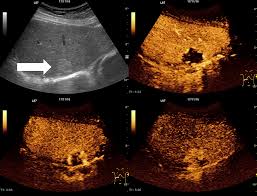

Imagen armónica

El ecógrafo escanea imágenes al doble o múltiplos de la frecuencia. Se usa para disminuir los artefactos (reverberación). También se encarga de mejorar la definición y se encuentra por defecto en la mayoría de los aparatos comercializados.